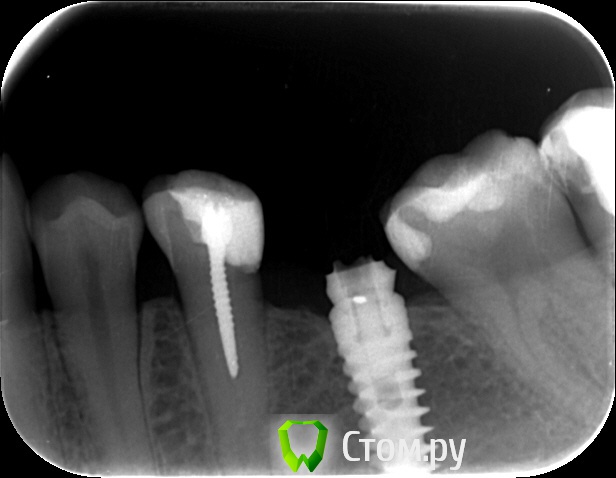

an_ver Опубликовано 29 мая, 2014 Поделиться Опубликовано 29 мая, 2014 Кто то пытался достать))) Абатмент спили в ноль...головку винта своротили.Набор Нео 3 Ссылка на комментарий

molchanoff Опубликовано 29 мая, 2014 Поделиться Опубликовано 29 мая, 2014 анкерок в пятерке в нерве стоит. Ссылка на комментарий

an_ver Опубликовано 29 мая, 2014 Автор Поделиться Опубликовано 29 мая, 2014 анкерок в пятерке в нерве стоит.Ага))) пациентка говорит лет 10-15 как стоит))) Ссылка на комментарий